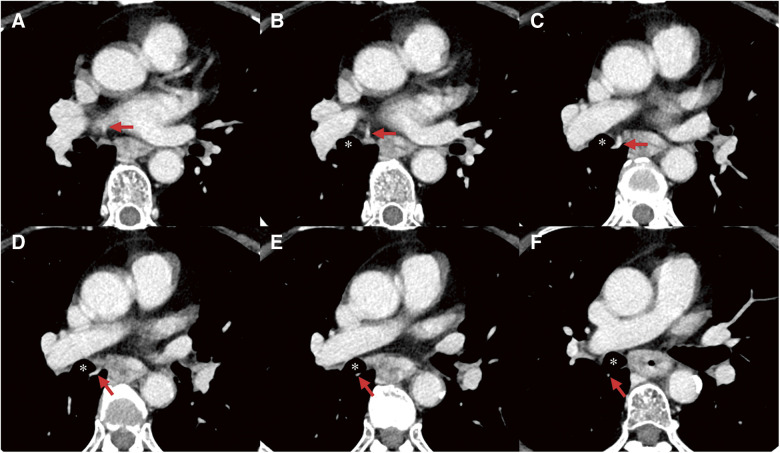

一名68岁女性被诊断为临床T3N1M0中胸食管癌。术前三维计算机断层扫描显示右上后肺静脉(RSPPV)异常,位于右中间支气管后方。患者行胸腔镜食管切除术并纵膈淋巴结清扫术。在我们开始解剖右侧隆突下淋巴结之前,我们静脉注射吲哚菁绿以确定异常RSPPV的运行位置,我们能够准确地确定其位置,正确识别血管和周围组织之间的差异。尽管患者在异常血管附近有淋巴结转移,并且由于粘连紧密,剥离手术很困难,但术中荧光成像使我们能够在没有任何多余血管损伤的情况下进行剥离。在这种情况下,术中荧光成像非常有用,可以提供关于异常位置的准确术中信息,促进更安全的手术。

A 68-year-old woman was diagnosed with clinical T3N1M0 middle thoracic esophageal cancer. Preoperative three-dimensional computed tomography indicated a right superior posterior pulmonary vein (RSPPV) anomaly, which ran behind the right intermediate bronchus. The patient underwent thoracoscopic esophagectomy with mediastinal lymph node (LN) dissection. Before we began the dissection of the right subcarinal LN, we administered indocyanine green intravenously to confirm the running position of the anomalous RSPPV, and we were able to ascertain its placement accurately with correct recognition of the difference between the blood vessels and surrounding tissue. Although the patient had LN metastasis adjacent to this anomalous vessel and the dissection procedure was tough due to tightly adhesion, intraoperative fluorescent imaging enabled us to perform the dissection without any superfluous vascular injury. Intraoperative fluorescent imaging is very useful in such cases, providing accurate intraoperative information on the location of the anomaly and facilitating safer surgery.